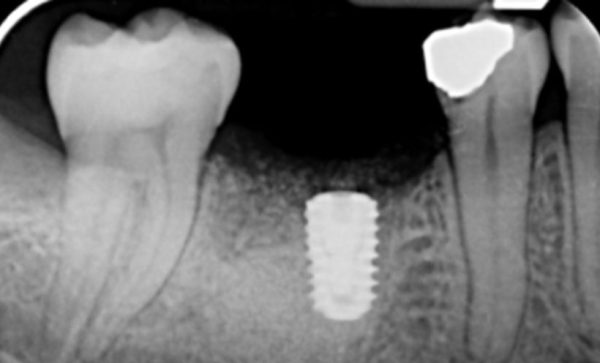

Case 46